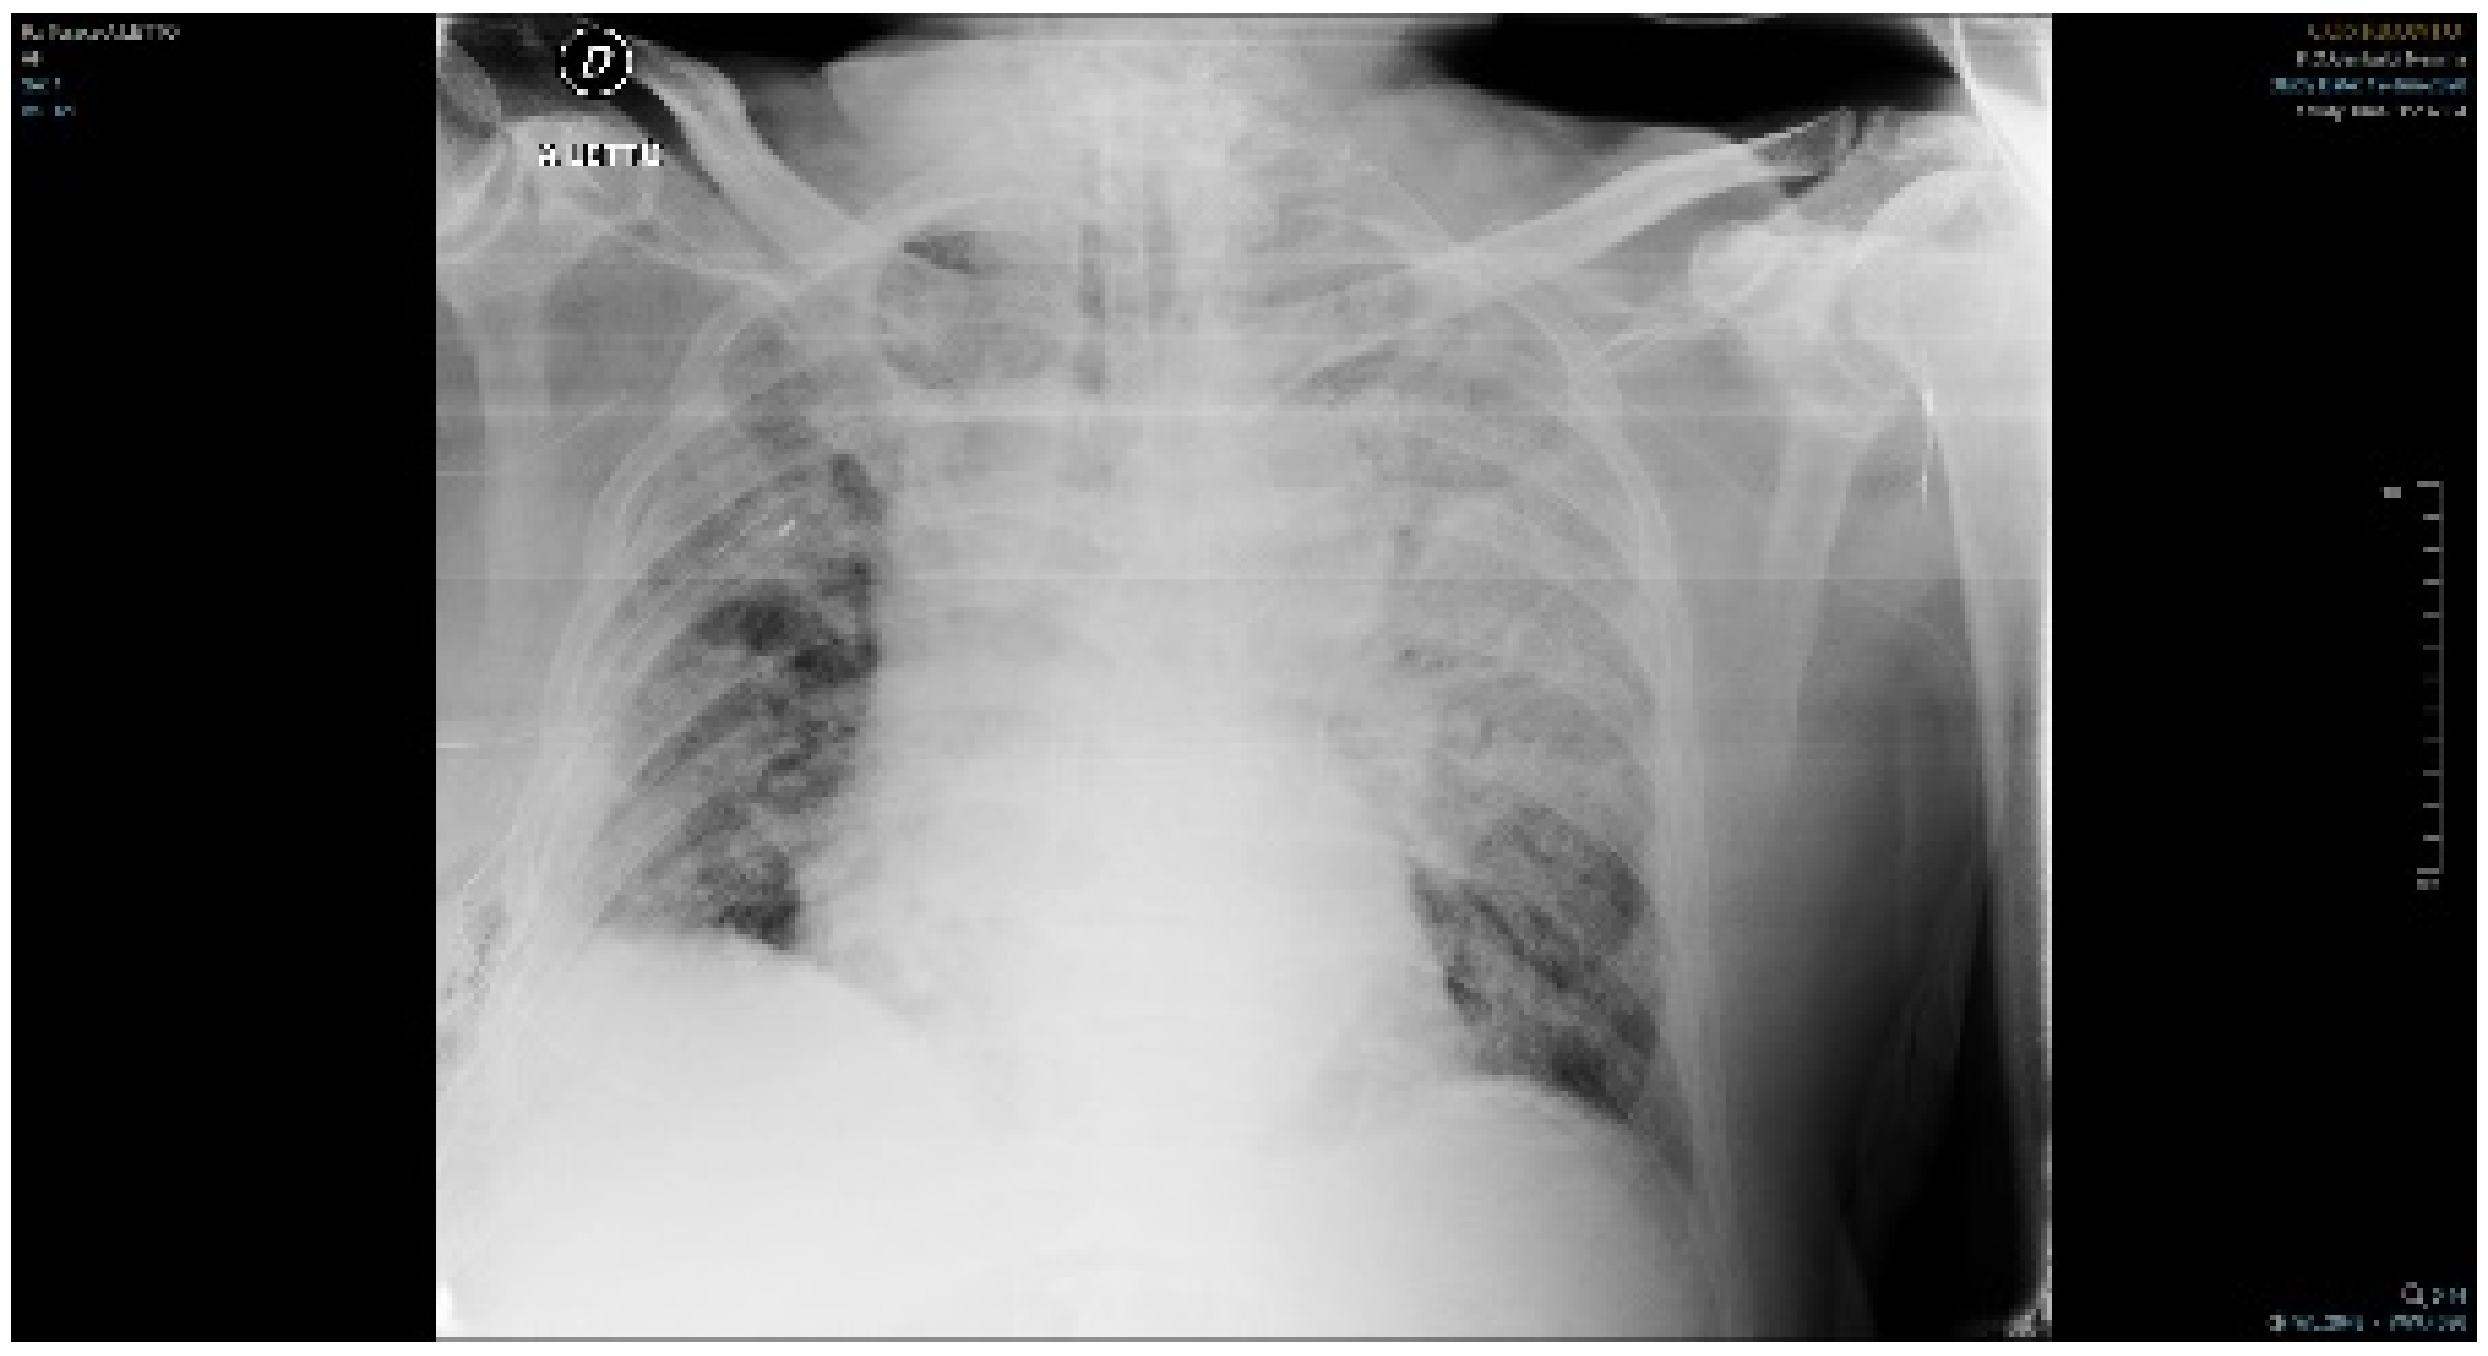

2. Case Report and Results